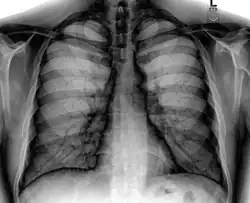

A normal posteroanterior (PA) chest radiograph of someone without any signs of injury. Dx and Sin stand for "right" and "left" respectively.